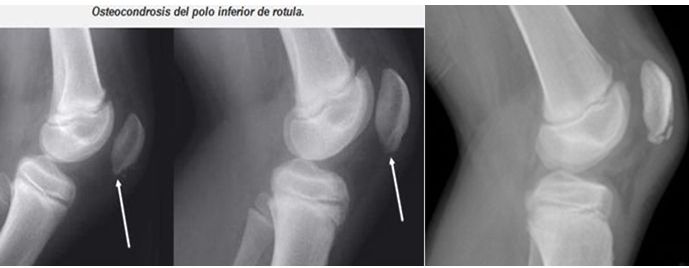

Esta apofisitis por tracción se desarrolla debido a la fuerza del tendón rotuliano en el polo inferior de la rótula. A diferencia de OSD, SLJ parece tener una predilección por los varones más que por las mujeres, y se observa en adolescentes activas entre las edades de 10 y 13 años. Debido a su madurez esquelética más temprana, las mujeres se ven afectadas a una edad más joven en comparación con los varones.

El síndrome de Sinding-Larsen-Johansson tiene una patogenia similar a la de la enfermedad de Osgood-Schlatter y los dos trastornos a veces se producen al mismo tiempo. El síndrome de Sinding-Larsen-Johansson es causado por el aumento de la tensión y de presión, debido a la tracción repetitiva por el tendón rotuliano en el polo inferior de la rótula (todavía en parte cartilaginosa en adolescentes) durante la contracción de los músculos cuádriceps.

Esto conduce a daños en los cartílagos, la hinchazón y el dolor, especialmente después de un esfuerzo excesivo, y más tarde al engrosamientodel tendón y la fragmentación del polo inferior de la rótula, y en ocasiones la inflamación de la bursa, situada entre el tendón y la rótula.

El síndrome se observa en adolescentes por lo general entre10 y 14 años deedad, pero es más frecuente en los hombres que practican deportes (fútbol, carrera, voleibol, gimnasia).

Los pacientes se quejan de dolor en el polo inferior de la rótula, sobre todo actividades como correr y saltar. Los casos graves pueden conducir a dolor subiendo y bajando escaleras, o incluso el desarrollo de una marcha antiálgica para caminar.

Las radiografías pueden demostrar calcificación irregular en el polo inferior de la rótula o pueden ser normales, especialmente en un paciente más joven que aún puede no tener una apófisis visible presente en la radiografía. Por lo tanto, los hallazgos de la historia y examen físico clásicos pueden, y deben, ser utilizados para hacer el diagnóstico, con las radiografías reservadas para casos atípicos u otras características relativas.